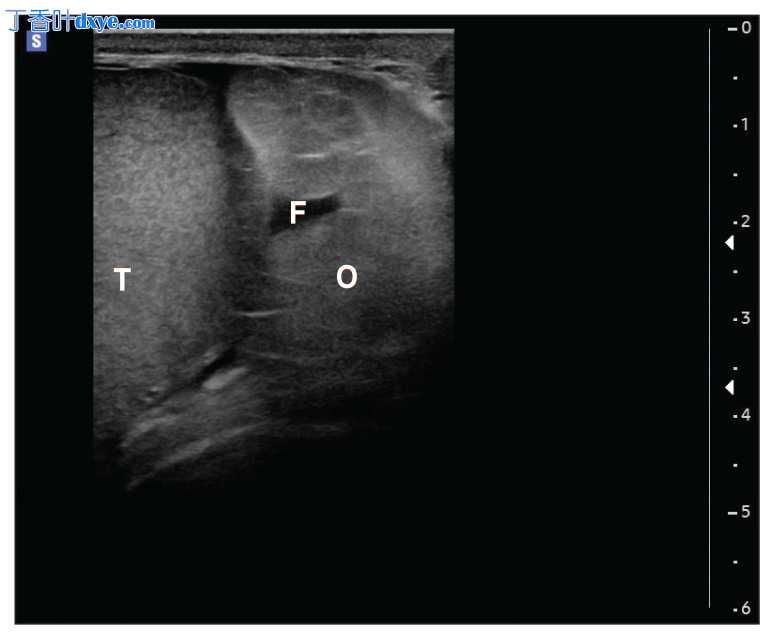

图 2

患者阴囊左侧近半部分的横向超声视图。左侧睾丸 (T) 的外侧是网膜 (O) 和少量游离液体 (F) 的积聚。